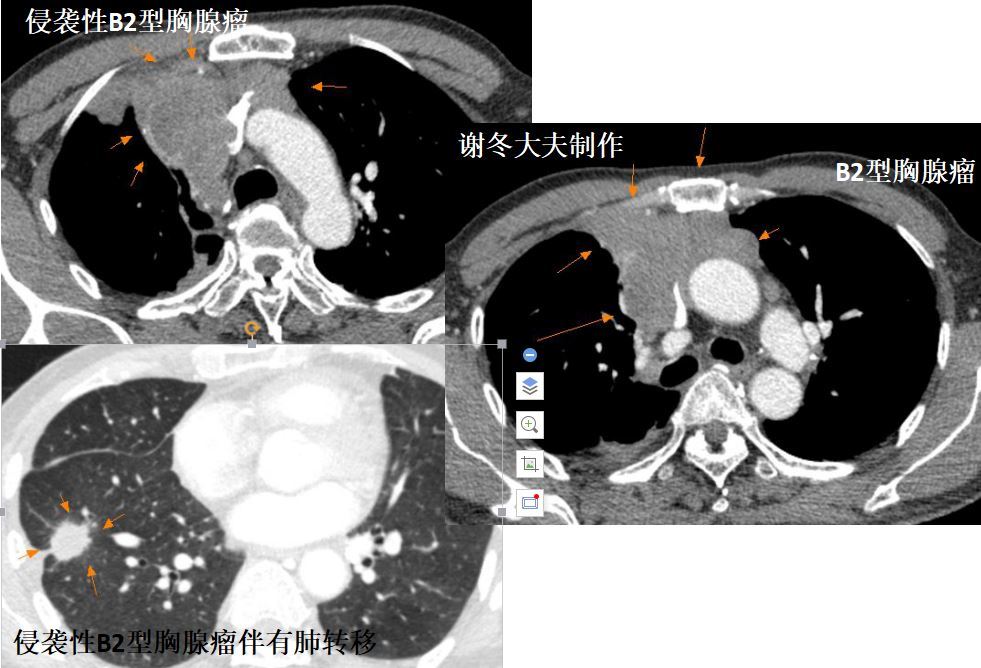

2.侵袭性胸腺瘤

侵袭性胸腺瘤明确的CT征象:纵隔结构的包绕,直接侵犯中心静脉、心包或胸膜种植转移和晚期发生的跨膈肌扩散。

1.多数胸腺瘤是低度恶性肿瘤,但少数胸腺瘤表现为侵袭性病变,可以侵犯大血管,包括无名动脉,上腔静脉,肺动脉等,也可以出现转移,包括胸腔内转移,肺转移,胸膜转移,锁骨上淋巴结转移,甚至脑转移,骨转移等。